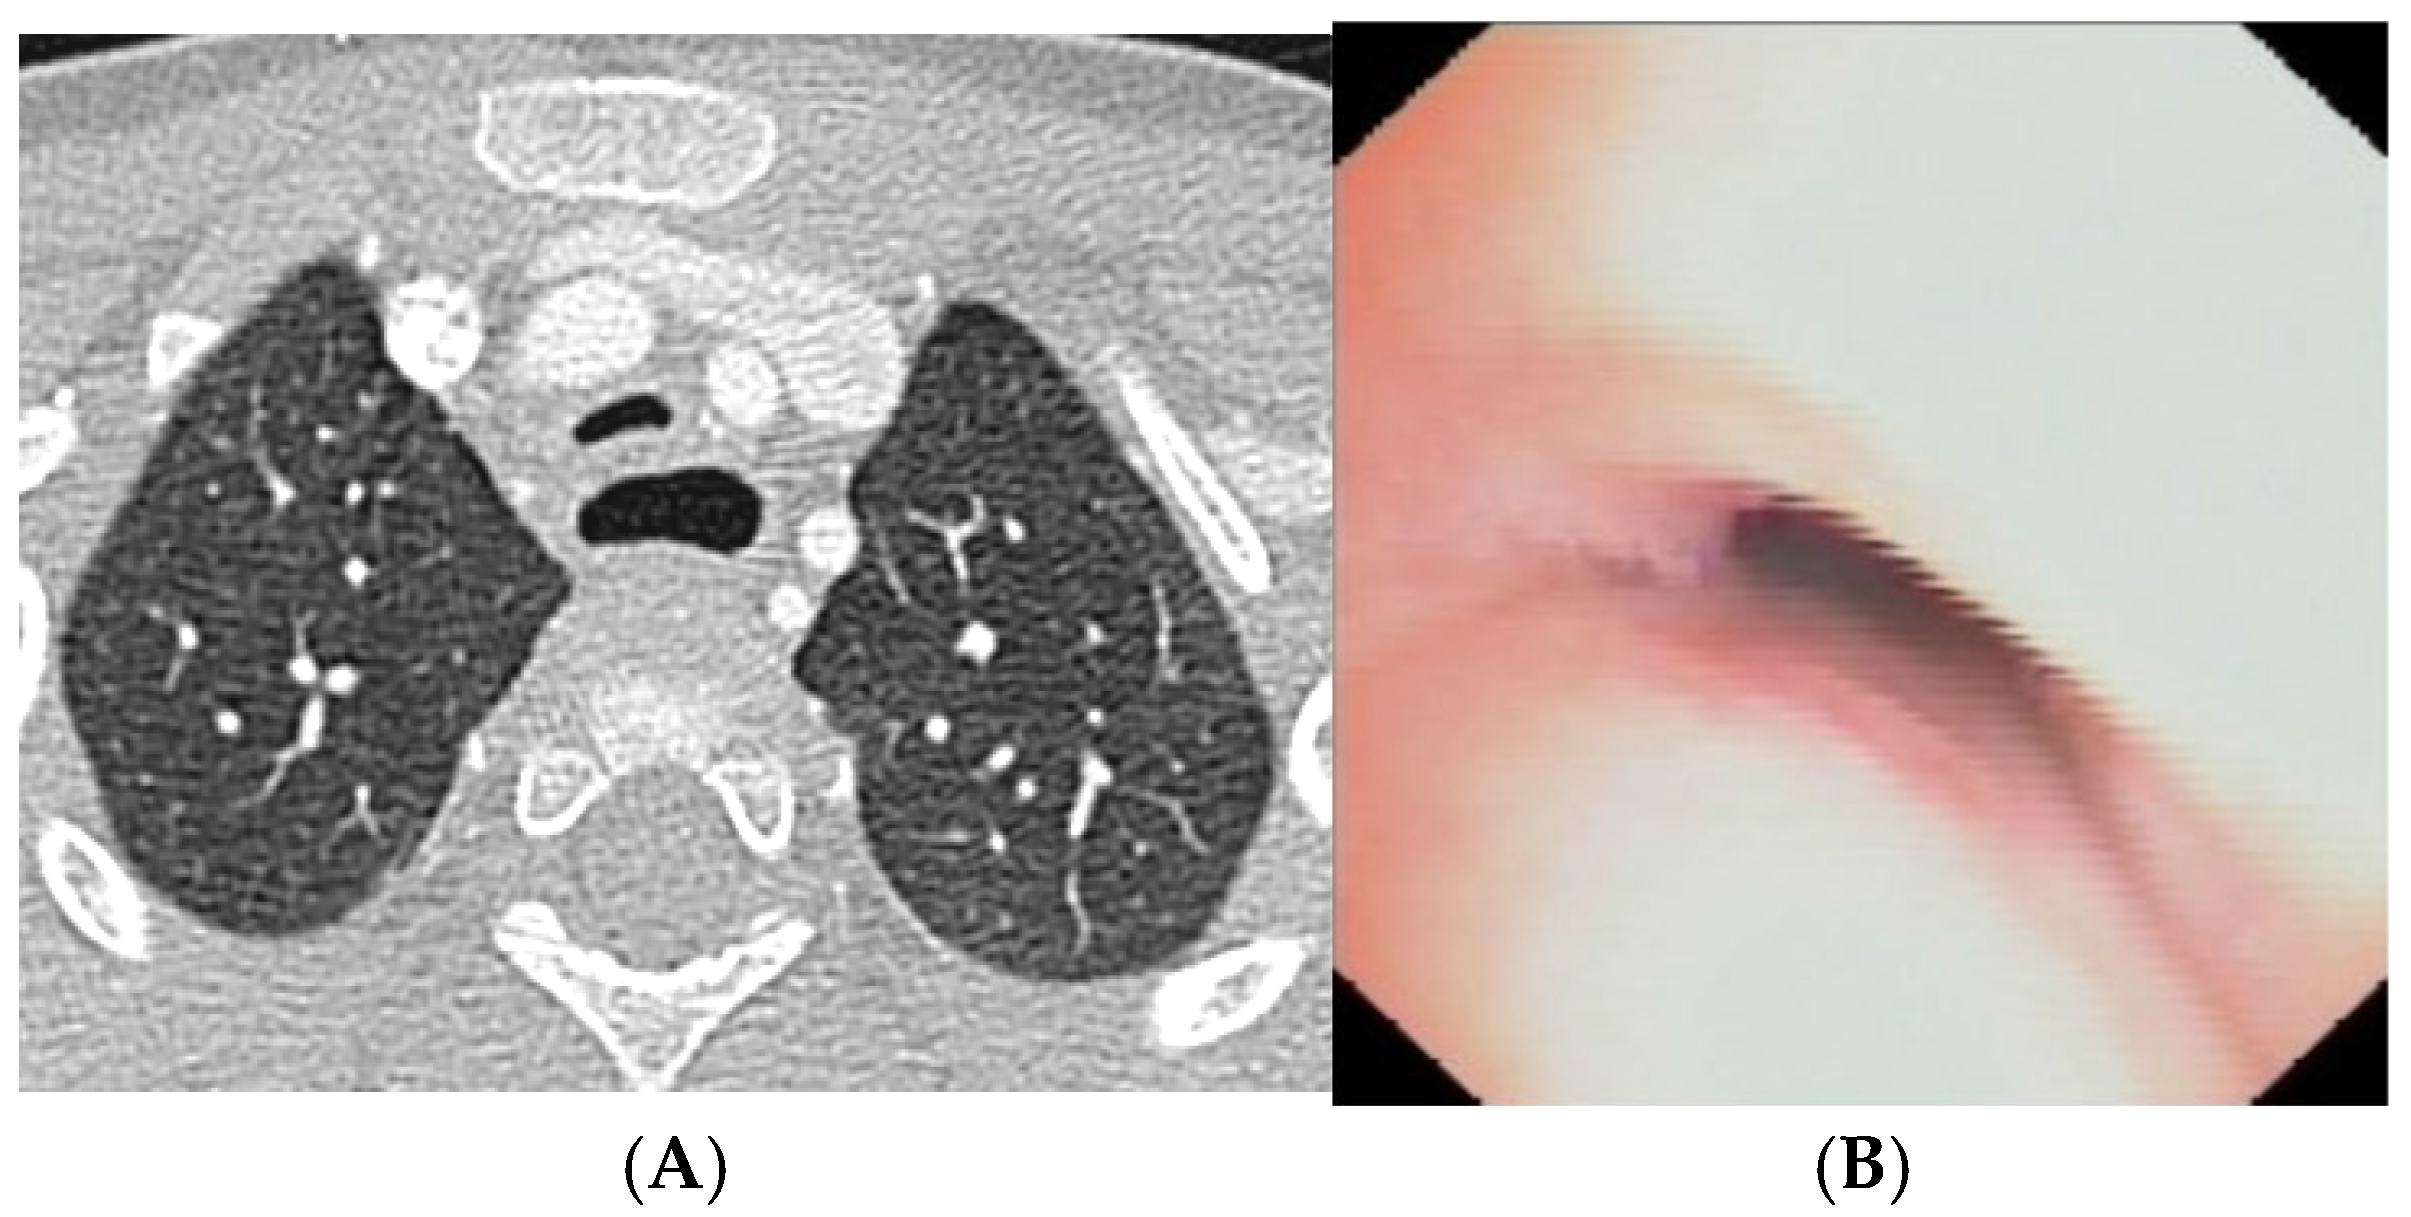

CLINICAL CASE 3: girl, 15 years old, clinical history of biphasic cough and recurrent respiratory infections. Already diagnosed with asthma with various inhalation therapies without clinical benefit. The patient was valuated with:

Figure 5.

A) Chest CT with CM: slight tracheal compression from IA. Fig. B) SVBS: well-preserved tracheal lumen up to junction between middle and distal third where clear pulsating extrinsic compression from IA deforms tracheal lumen and granulomas are present on pars membranacea at this level. Fig. C) DVBS: when patient performs abdominal straining, pars membranacea appears hypermobile and protrudes pathologically into tracheal lumen, which at level of extrinsic compression becomes completely occluded by contact between pars membranacea and anterior wall. The presence of granulomas at this level proves this contact occurs recurrently. Abbreviations. CT: Computed Tomography; CM: Contrast Medium; SVBS Static Videobronchoscopy; IA: Innominate Artery; DVBS: Dynamic Videobronchoscopy.

After collegial discussion with the TT: OAA was performed (see “Surgical Treatments” later). At the clinical follow-up one year later: less frequent infectious episodes, but still present biphasic cough attacks.